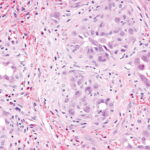

Angiolymphoid hyperplasia with eosinophilia (ALHE) shows characteristic histologic features, including a proliferation of small blood vessels, many of which are lined by enlarged endothelial cells with uniform ovoid nuclei and intracytoplasmic vacuoles. These distinctive endothelial cells have been described as having a cobblestone appearance. In addition, a perivascular and interstitial infiltrate composed primarily of lymphocytes and eosinophils (see the image below) is present. Eosinophils typically comprise 5-15% of the infiltrate. Rarely, they can account for as much as 50% of the infiltrate. Occasionally, the infiltrate is devoid of eosinophils. Lymphoid aggregates with or without follicle formation are typical.